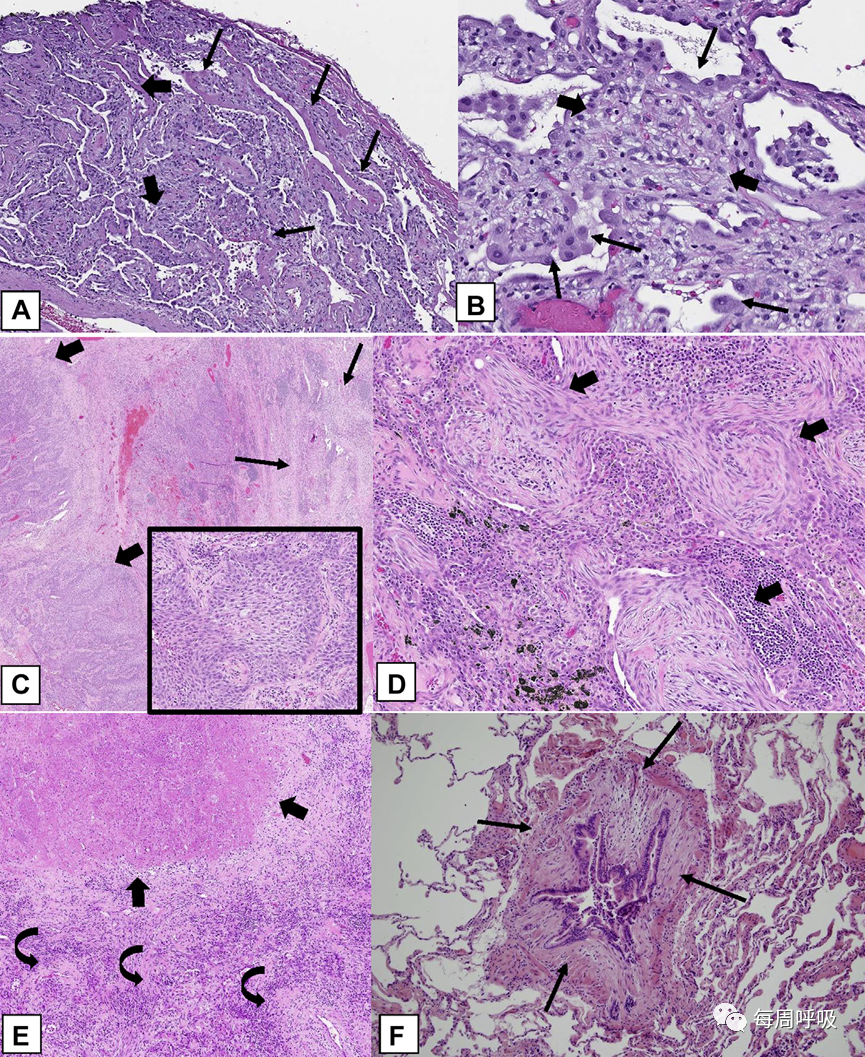

有三种罕见的与OP相关的组织学模式(表3):(1)瘢痕性OP(图23A、23B),(2)AFOP(图23C、23D),(3)肉芽肿性OP(23E、23F)。这些罕见的组织学模式具有不同于COP、SOP和FOP的临床特征。

瘢痕性OP的管腔结缔组织息肉样栓子与COP相同,但也含有致密的纤维胶原蛋白,而不是通常OPP所特有的纯粹由疏松结缔组织组成(图23A, 23B),可能与树状骨化有关(图23A)。AFOP组织学模式可出现在一系列临床环境中,从可能类似于COP或SOP的相对惰性的临床表现,到炎症的患者可出现呼吸衰竭,以及提示该疾病更符合弥漫性肺泡损伤的临床表现。在后一种情况下,可能存在病例样本采集问题,即在肺活检标本中无法获得更明确的DAD组织学特征。肉芽肿性OP是另一种不常见的发现,活检标本显示OPP和非干酪性肉芽肿性炎症混合存在。在这种情况下,应格外小心,以排除感染、结节病、胶原血管疾病或药物毒性。坏死性肉芽肿的存在倾向于感染。

图23罕见的组织学模式:瘢痕性OP模式(OPP)、AFOP以及肉芽肿性OP (GOP)。A, B,瘢痕性OPP。该活检标本显示远端气道内结缔组织的息肉样栓子,但大部分由嗜酸性致密胶原(粗箭头)组成。这种致密的纤维组织与OPP中常见的邻近疏松的纤维组织(细箭头)形成对比。此外,还有与远端气腔内息肉样栓相关的骨状结构,呈树突样骨化(弯曲箭头)。C, AFOP。该活检标本显示许多气道内(箭头所示)广泛的纤维蛋白和明亮的嗜酸性表现,以及疏松结缔组织的息肉样栓子。D,该活检标本中的大多数肺泡腔显示除OPP病变外远端气腔有嗜酸性纤维蛋白(粗箭头)聚集。E,GOP。活检标本显示除了多发性非干酪性肉芽肿(粗箭头)外,还有结节状浸润,提示OPP。F,高倍镜显示远端气腔内疏松结缔组织的腔内息肉样栓子(细箭头),邻近圆形上皮样组织细胞形成的非干酪性肉芽肿(粗箭头)。